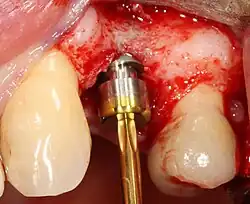

The implant fixture is turned into the osteotomy. Ideally, it is completely covered by bone and has no movement within the bone.